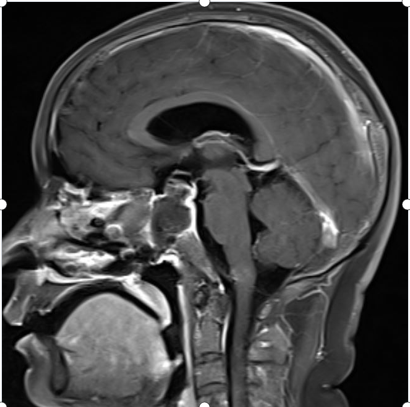

术前核磁共振提示垂体瘤复发

T2像提示肿瘤质地不均